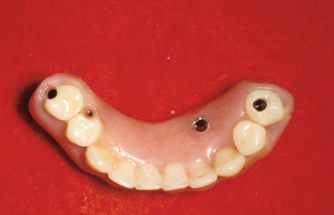

As an alternative to the relatively expensive traditional hybrid restoration that the senior population may perceive as unattainable at their age, an immediate-load all-resin provisional may often be a reasonable option as an entry-level prosthesis. This can serve for extended periods or indefinitely, and when made with a sufficient volume of resin and opposing a light occlusion such as a maxillary denture, it can offer the benefit of fixed retention at a significant reduction in expense (Figure 15 and Figure 16). Technology involving a guided approach for placing three implants universally in the same sites with pre-manufactured, one-size-fits-all bar components in the mandible can now allow placement of a final restoration in one day, again at a significantly reduced cost (Figure 17 and Figure 18).24-26 Both of these fixed options—the resin long-term provisional and the three-implant bridge—are economically comparable to the most commonly considered implant prosthesis for elderly patients, the two-implant overdenture. In contrast to the latter, however, both fixed restorations offer significant advantages in bite force, bone preservation, maintenance, and patient satisfaction that are simply unachievable with the removable implant overdenture prosthesis.27-31

Fig 17. A three-implant fixed bridge may be an immediate-load alternative for a fixed restoration as opposed to a two-implant overdenture. In addition to significant cost reduction due to pre-manufactured components, the final long-term restoration is delivered on the day of surgery.

Figure 17

Fig 18. A three-implant fixed bridge may be an immediate-load alternative for a fixed restoration as opposed to a two-implant overdenture. In addition to significant cost reduction due to pre-manufactured components, the final long-term restoration is delivered on the day of surgery.

Figure 18